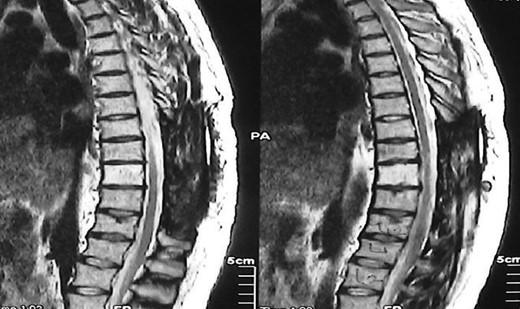

A 30-year-old male patient was admitted to our clinic with back pain. Pain was provoked by movements. The severity of pain was associated with the inability to perform the activities of daily living. The patient did not have any lymphoma-related B-type symptoms, including body weight loss, fever and sweat at night. He did not have a past and family history. There was no neurological deficit. Routine laboratory test results were normal. A magnetic resonance imaging (MRI) scan of the thoracic spine demonstrated an epidural tumor at the T9–11 level (Figs 1–3). The patient underwent spinal cord decompression via total laminectomy of T9–11 levels. Subtotal resection of the tumor was performed. Histological examination revealed the polymorphous cellular infiltration by histiocytes, large mononuclear cells and lacunar Reed–Sternberg cells with folded multi-lobed nuclei and small nucleoli (Fig. 4). Immunohistochemical staining was positive for CD15 and CD30 and negative for CD3, CD20, CD79a or CD45Ro. These features were most frequently observed in the mixed cellularity type of Hodgkin's lymphoma. Histological examination of the vertrebral body revealed no abnormality. The results of all other examinations (F-18 fluorodeoxyglucose positron emission tomography (F-18 FDG PET/CT), bone marrow biopsy and computed tomography (CT) of the chest, abdomen and pelvis) were negative for an occult disease. The patient was referred to the hematology department to undergo staged treatment. Six courses of chemotheraphy containing ABVD regimen (adriamycin, bleomycin, vinblastine and dacarbazine) were given to the patient. Postoperative MRI scan did not reveal any evidence of Hodgkin's disease (Fig. 5), F-18 FDG PET/CT, CT of the chest, abdomen and pelvis were obtained in 24 months and did not reveal any evidence of Hodgkin's disease.

Moridaira et al. [4] reported a case of Hodgkin's disease at T8–10 epidural space. Rao et al. [6] published a case with primary spinal epidural Hodgkin's lymphoma. Our case is apparently the seventh case to be diagnosed with Hodgkin's disease who presented with spinal cord compression due to epidural space without lymphoma elsewhere. The abnormal MRI marrow signal of the T9 and T10 vertebral bodies can be seen in Fig. 5. Maybe the tumor in fact originated within the abnormal T9 or T10 bone marrow and spread to the epidural space via the epidural venous plexus. But histological examination of the vertebral body revealed no abnormality.